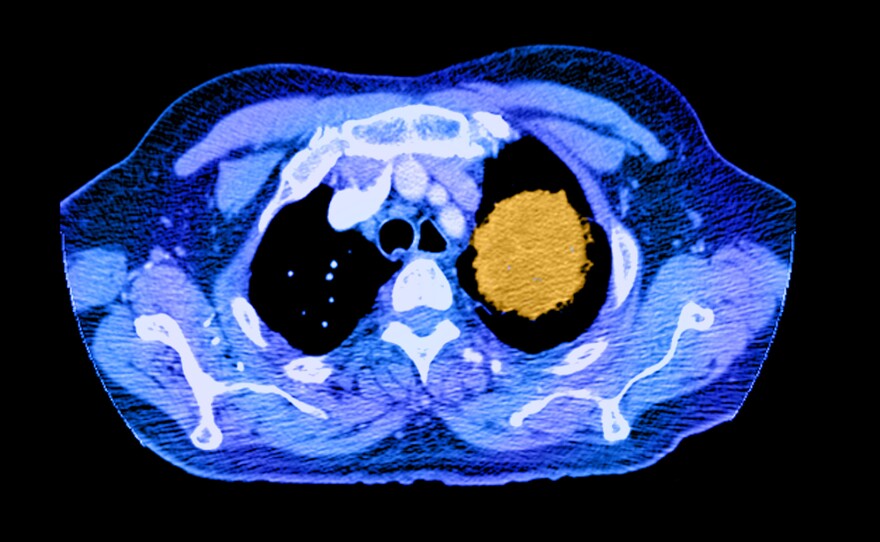

A color-enhanced spiral CT image of the chest shows a large cancerous mass (in yellow) in the left upper lobe.

Medical Body Scans Science Source